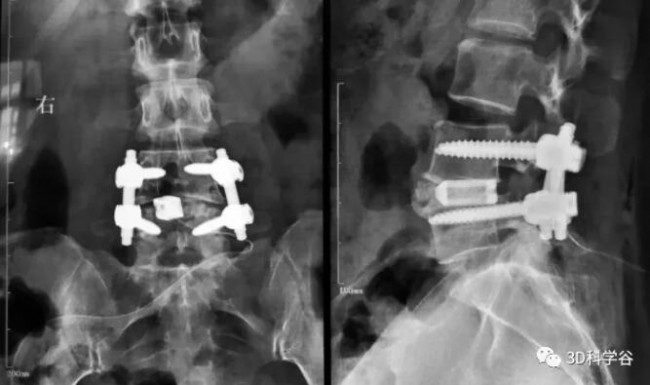

This approved3D printingIntervertebral fusion cage: The pore diameter is 300-800μm, and the porosity is 70-80%. It is the first domestic fusion cage product without bone grafting window using additive manufacturing technology. It has good biocompatibility and elasticity like cancellous bone. Modulus, surface microporous structure provides good initial stability.

At the same time, the product has multiple models and specifications that can meet a variety of surgical needs. The use of the product conforms to the operating habits of the fusion cage, allowing clinicians to quickly adapt to the product’s intraoperative implantation and surgical promotion.